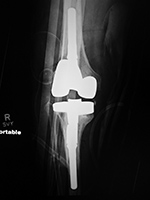

| Posterior cruciate retaining total knee prosthesis with cementless femoral and cemented tibial component and patellar resurfacing |

Stryker Triathlon PSC total knee arthroplasty

- posterior cruciate removal prosthesis |

| There is a postoperative drain and skin staples. From Taljanovic, 2005 |

There is also a surgical drain and skin staples in place. 65 year-old woman. |